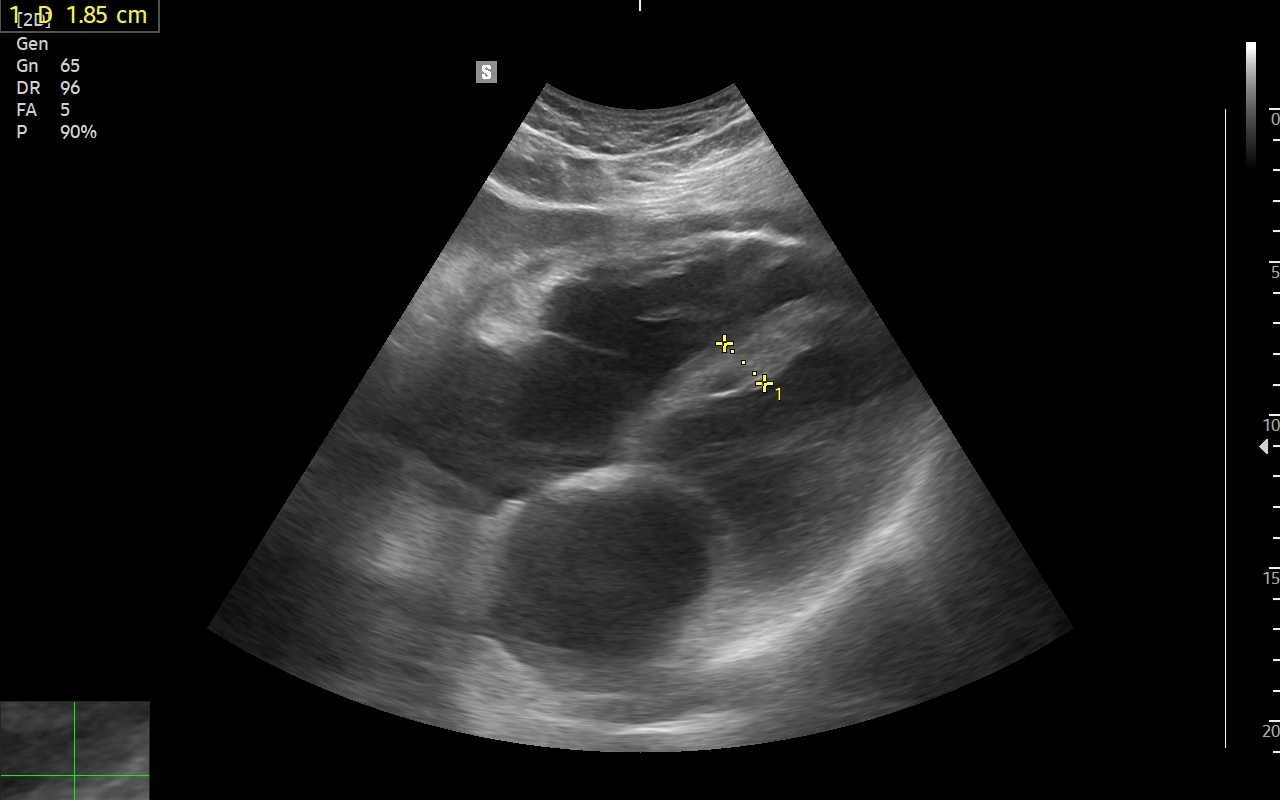

Badanie echokardiograficzne, nazywane także echo serca lub USG serca jest jedną z podstawowych metod diagnostyki kardiologicznej. W badaniu tym ocenia się zarówno morfologię narządu, jak i jego funkcję w postaci pomiarów wielkości jam serca, grubości mięśnia sercowego, czynności skurczowej oraz rozkurczowej lewej i prawej komory, oceny funkcji zastawek serca, wyglądu wsierdzia, osierdzia, a także w postaci pomiarów aorty, poszukiwania obecności patologicznych objawów sercowych związanych z chorobami innych narządów (np. choroby płuc, nadciśnienie tętnicze).

Wskazania do badania USG serca są bardzo szerokie i obejmują diagnostykę bólów w klatce piersiowej, przyczyn zmniejszonej tolerancji wysiłku, przewlekłego zmęczenia, duszności, obrzęków kończyn dolnych i wodobrzusza, ocenę powikłań nadciśnienia tętniczego i zawału serca, diagnostykę zaburzeń rytmu serca, zatorów tętniczych, udaru mózgu, diagnostykę przewlekłego kaszlu, utraty masy ciała, gorączki i powikłań anginy gardła w obrębie zastawek serca.